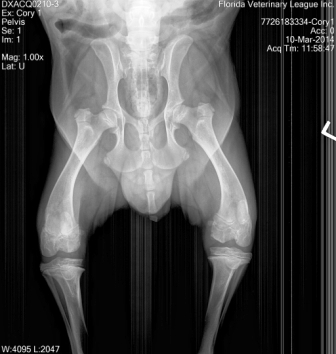

March 20, 2014

Cory is an unfortunate 7 month old puppy who was abandoned by his owner and unable to be adopted at an animal control facility due to a severe and debilitating defect on his hips and both rear knees/legs; Cory had two separate surgeries on each leg and He is able to walk now.

We are looking forward to providing this beautiful corgi baby with the opportunity to find a fantastic forever home.

Cory will never run or go for long walks like other dogs...He was also born with partial sight (vision) deficiency.Cory will always be a special need boy! Please stay tuned for future updates and thank you for supporting our rescue efforts!